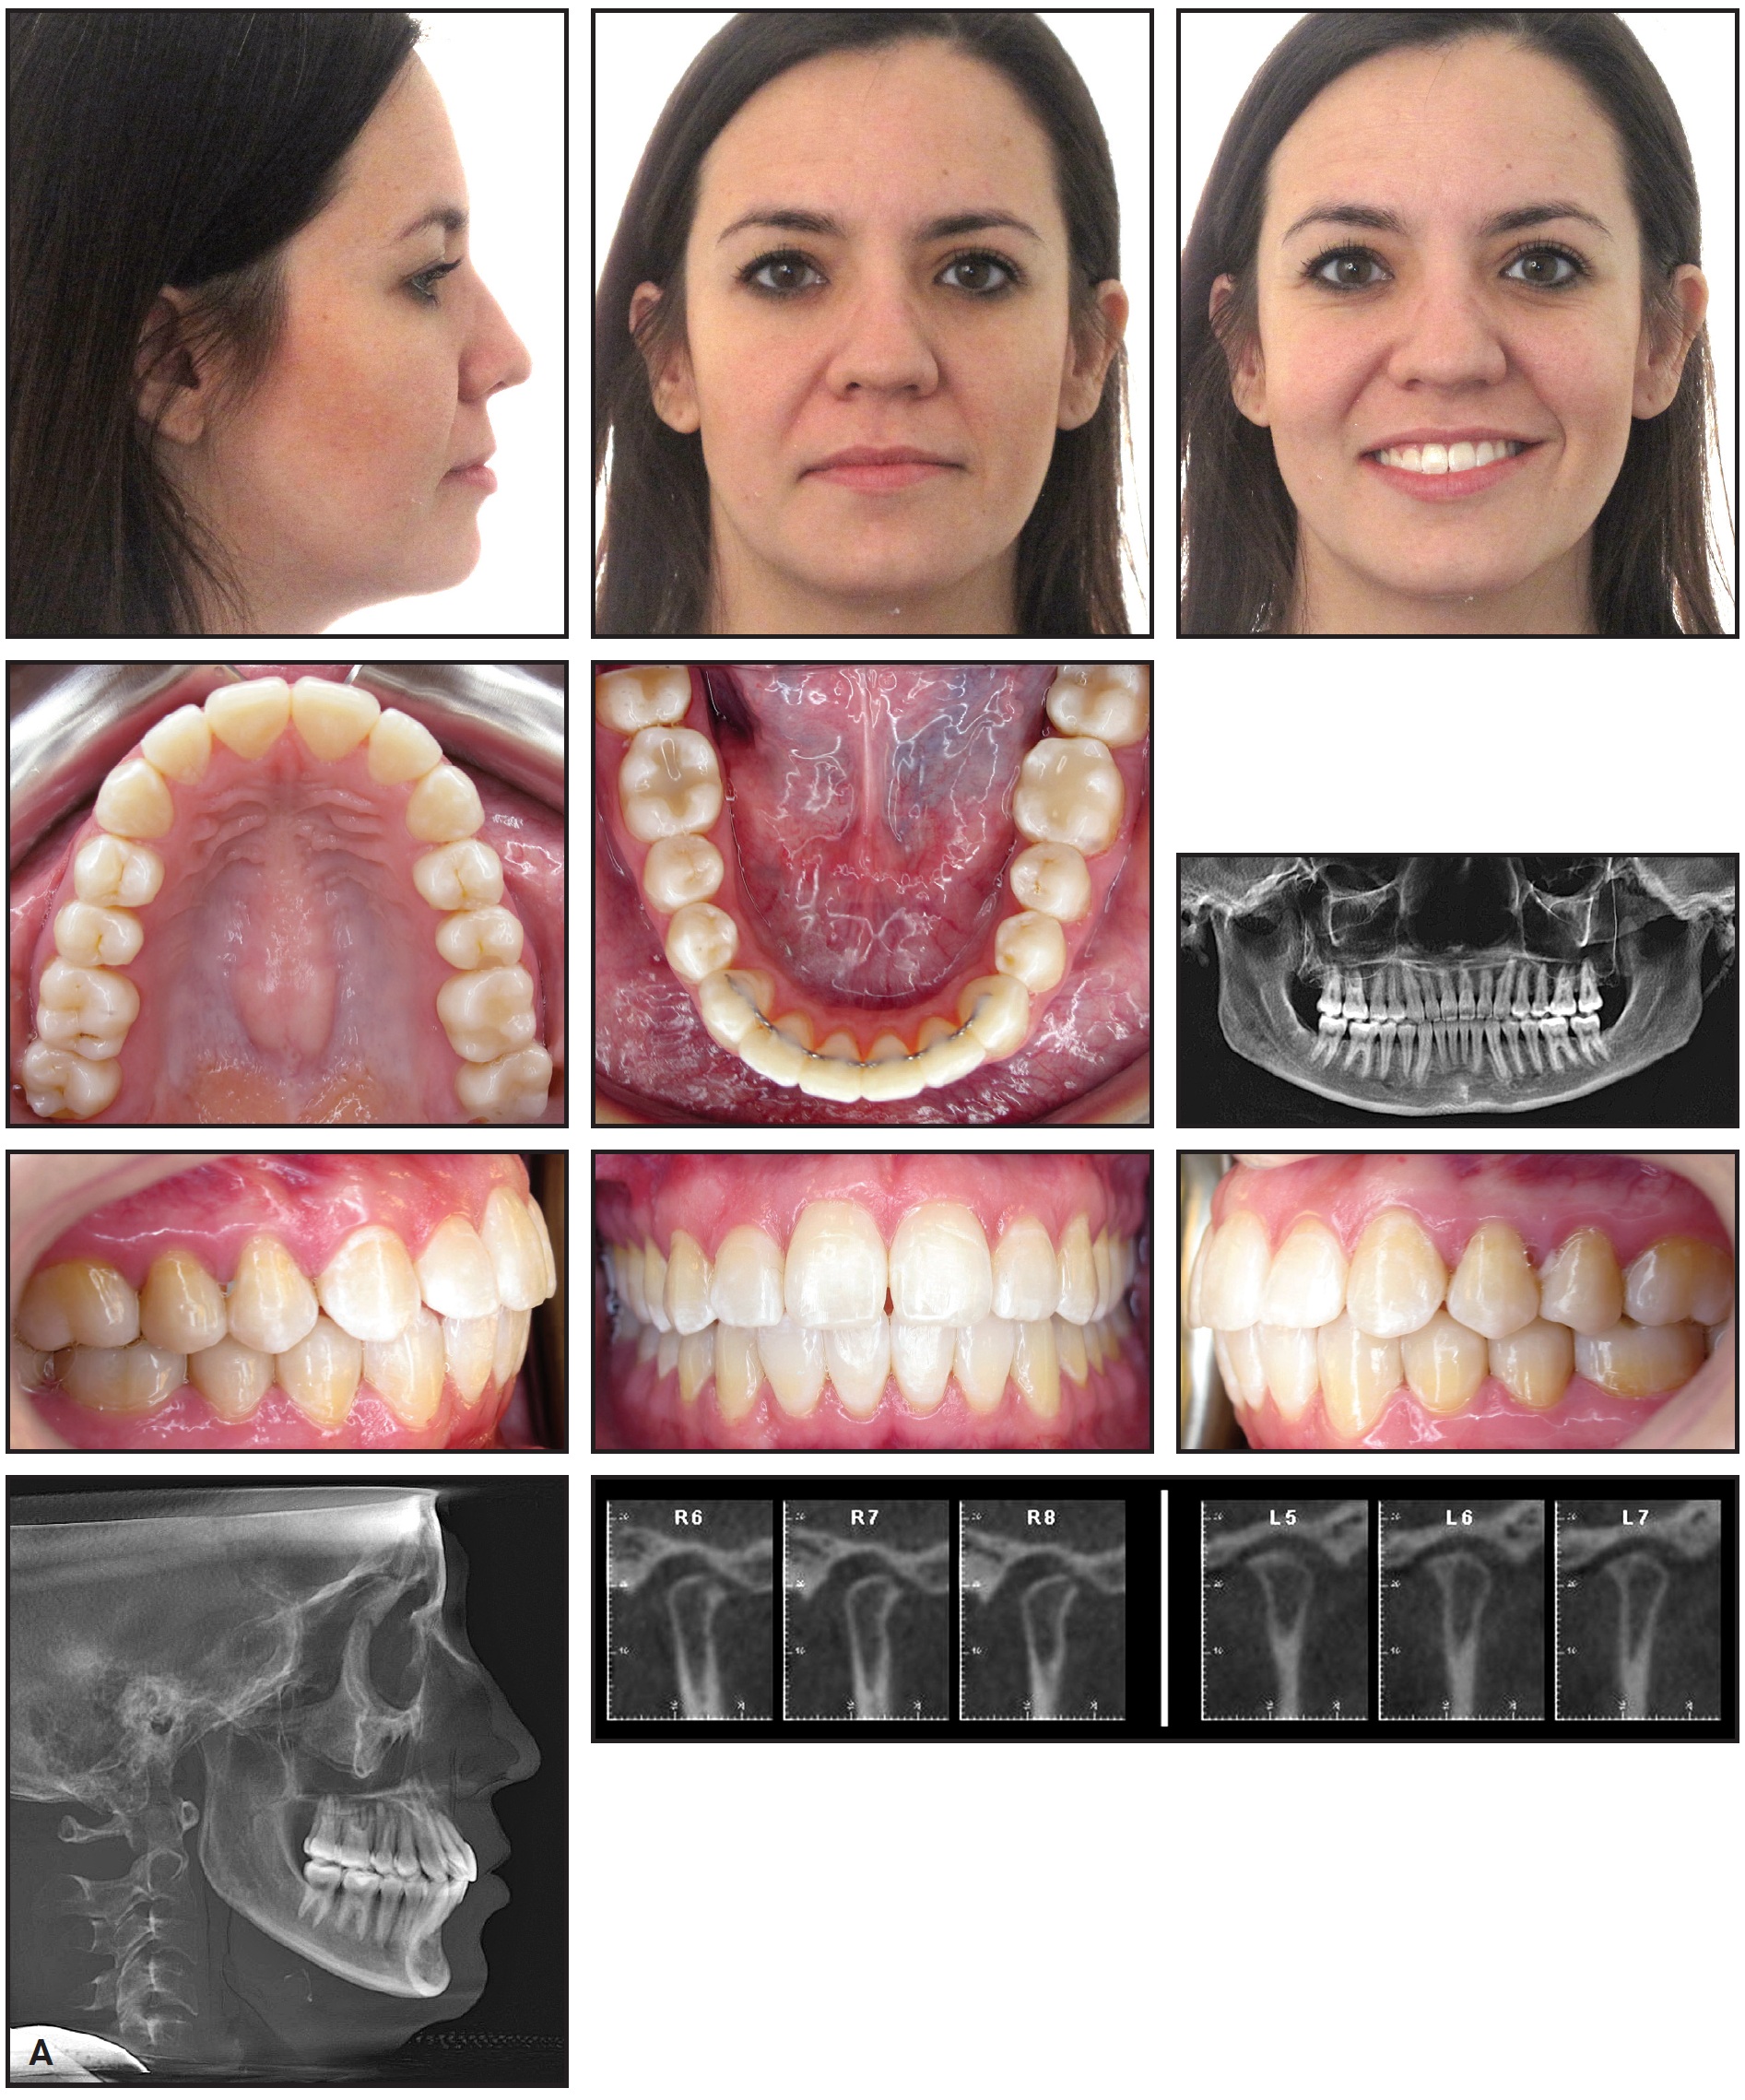

Orthodontic treatment was then initiated by bonding the maxillary arch. The archwire sequence progressed to .018" stainless steel over three months, and the lower first molars were allowed to erupt vertically into the occlusion (Fig. 5). Four weeks later, the orthotic was cut off distal to the second premolars, and elastics were prescribed from the upper to lower first molars while the patient wore the orthotic continuously.

Fig. 5 Maxillary arch bonded, with wire sequence progressing to .018" stainless steel over three months. Lower first molars allowed to erupt vertically into occlusion; note first molars in constructed bite without orthotic in place.

After two more months, the orthotic was cut off distal to the canines, and the lower first and second premolars were bonded to enable their vertical eruption (Fig. 6).

Fig. 6 Orthotic cut off distal to canines; lower first and second premolars bonded to enable vertical eruption.

Another three weeks later, a full archwire was inserted, with comfort tubing in the anterior region, and Class III vertical elastics were worn while the patient maintained orthotic wear from canine to canine (Fig. 7).

Fig. 7 Full archwire with anterior comfort tubing and Class III vertical elastics.